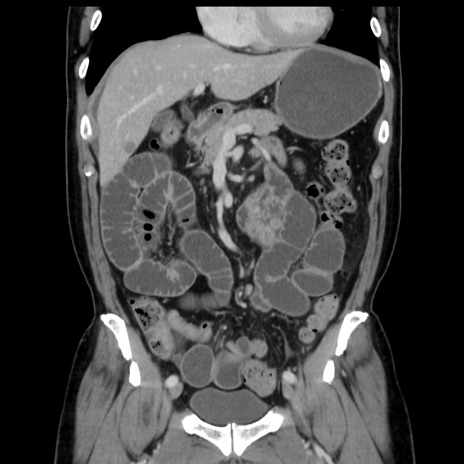

症例16(冠状断像)

【症例】 70歳代男性

【主訴】 腹痛、嘔吐

【現病歴】 約1ヶ月前より間欠的に腹痛と嘔吐あり、当院消化器内科を受診したところCTで多発する肝臓のLDAを指摘され、精査中であった。以降は消化器症状は安定していたが、2日前より嘔気と腹痛があり、同日より排便・排ガスが消失した。改善認めず、 本日、救急外来を受診した。

【既往歴】 大腸ポリープ切除後。

【身体所見】意識清明・会話良好、BT 36.3℃、BP 127/80mmHg、 P 80bpm、腹部:膨満あり、平坦・軟、上腹部正中および下腹部正中に圧痛あり、反跳痛なし、筋性防御なし。

【データ】WBC 7200、CRP 0.77